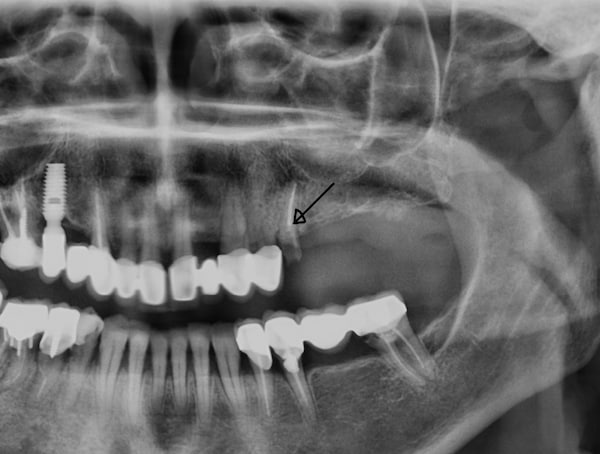

Η ανύψωση ιγμορείου είναι μια χειρουργική διαδικασία όπου ανυψώνουμε την μεμβράνη και τοποθετούμε υλικό οστικού μοσχεύματος